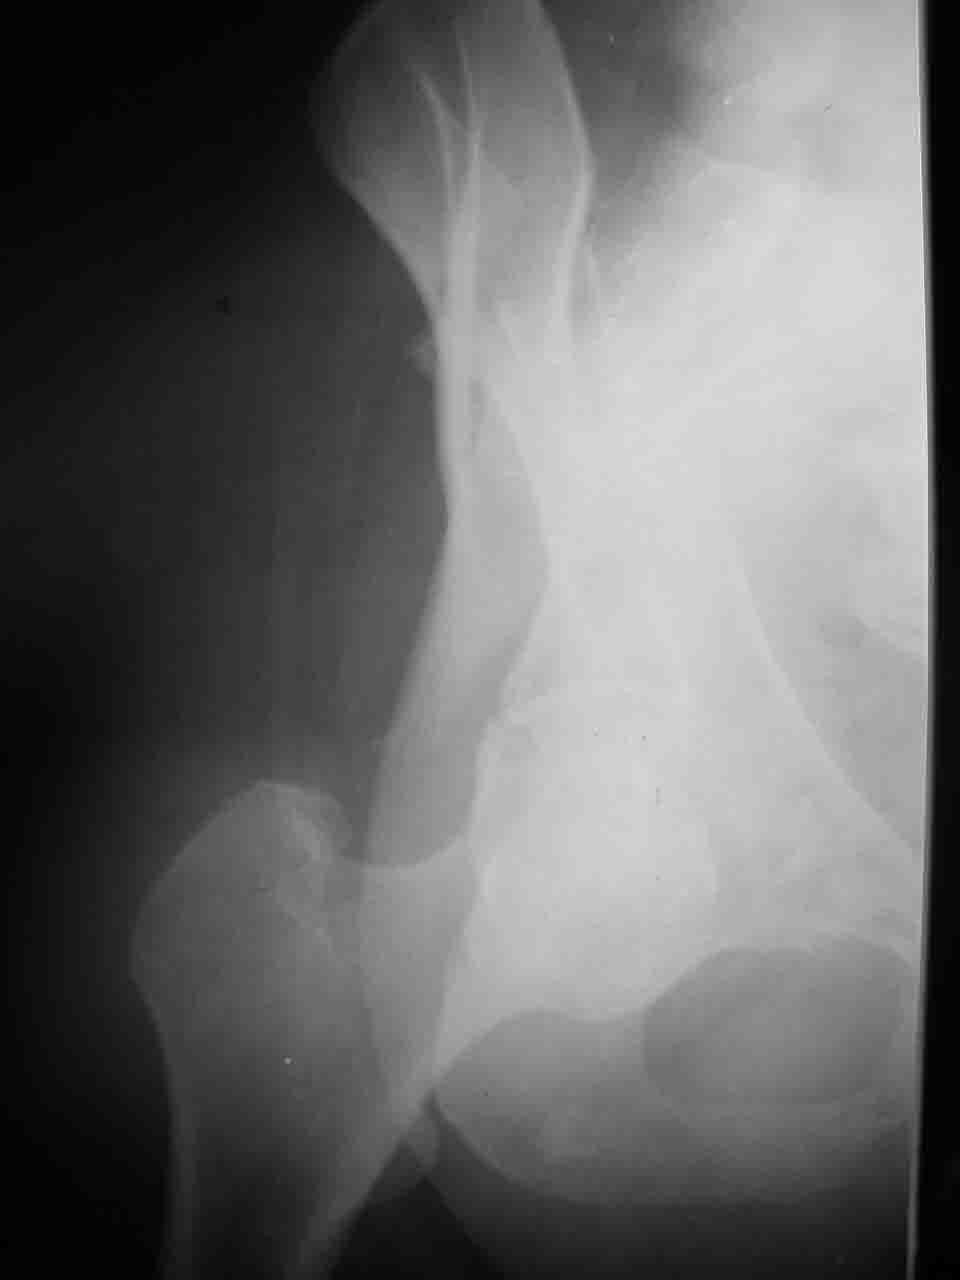

Вопрос доступа к вертлужной впадине при остеосинтезе задача не простая. Конечно, у Летурнеля и Тайла всё давно описано, нам остается только брать на вооружение. Но сами понимаете, что не бывает двух одинаковых ситуаций, поэтому в каждом случае вопрос решается сугубо индивидуально. Наша главная цель - восстановить анатомию с нанесением минимальной дополнительной травмы тазобедреннному суставу, думаю с этим никто не поспорит. Расширенный илиофеморальный доступ уж слишком травматичен (как сказал один коллега "таз лежит отдельно, больной отдельно").Стоит ли делать из пациента анатомический препарат для того чтобы легче ориентироваться. Да и нужно ли собирать всю "мозаику"? Мы применяли при таких операциях своеобразную операционную хитрость - сначала устраняли грубое смещение крыла под гребнем с фиксацией так называемой "плавающей" пластиной (временно фиксированной на двух винтах)- доступ или продлевали боковой, или делали небольшой дополнительный разрез над гребнем. Это позволяло устранить грубое смещение и захождение отломков тела повздошной кости, что значительно облегчало репозицию и остеосинтез впадины над сводом. Основное внимание конечно же уделяли нагружаемому задне-верхнему отделу. Сообщите ваш адрес, пришлю схемы и рентгенограммы.